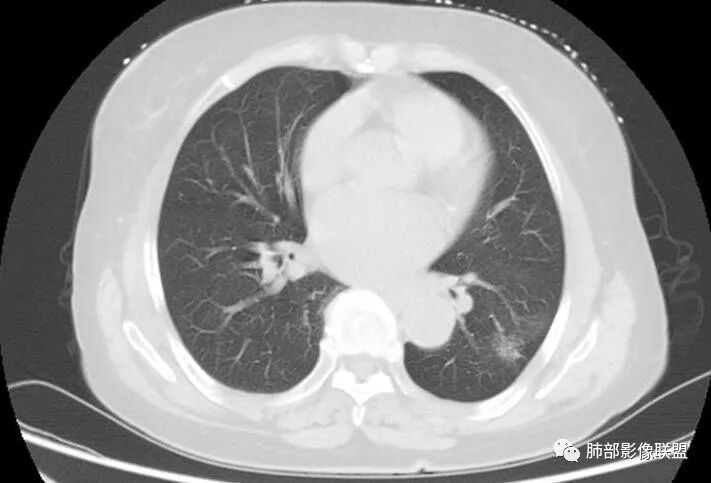

老年女性,气喘入院,发现左肺占位

睡神-阿豆豆:左肺下叶背段占位,边界尚清晰,有深分叶,有胸膜牵拉,有血管集束,支持恶性病变,不支持的如下,短毛刺不明显,病灶内有钙化。结核的话周围没有卫星灶。综合考虑肿瘤,鉴别结核。一切∮随缘:左肺结节,边缘光整,有分叶,轻度牵拉胸膜,形态规则,其内可见小片状钙化,增强后可见强化,病灶内似见小空泡,考虑:隐球菌,鉴别类癌蔡磊:左肺下叶占位,边缘较清,有深分叶,收缩牵拉线边缘光、清晰,内有钙化。与支气管关系不密切,增强后有强化,考虑恶性在前,错构、结核次选。M-Imaging :病灶边缘平直,其内斑片钙化,炎性肉芽肿,PC德芙~云味:左肺下叶占位,边缘较清GGO,有深分叶,边缘有膨隆有平直,胸膜牵拉,内有钙化。支气管近端有阻塞,有血管进入,增强后有强化,考虑恶性,待排隐球。丽:左肺下叶病变,边缘模糊不清,可见深分叶,内粗大钙化,轻度强化,不除外恶性可能飞鹰行动:左肺下叶病灶,有膨胀性表现,可见分叶征象,内部钙化位于一侧,见可疑小泡征,相邻叶间胸膜增厚,增强后可见血管穿入,其血管边缘毛糙,考虑恶性病变,腺癌,鉴别结核。巴伟:首先支持炎性红日东升:左肺下叶结节,边缘较光整、清晰,有分叶,外缘轻度牵拉胸膜,总体形态偏平直收缩,其内可见类圆形规则钙化(面积大于10%),增强轻度强化并见血管显影。考虑良性病变,炎性肉芽肿。平安是福:左肺下叶结节,轻度分叶,病灶内见钙化,血管穿行,中度均匀强化,边缘可见胸膜凹陷及平直,考虑结核,PC,鉴别诊断腺癌。Lotus:炎性可能性大,结核?张小兵:病灶整体以收缩为主,考虑炎性肉芽肿RockJ-ason:考虑炎性病变,鉴别腺癌张延军:左下肺结节,边缘平直,伴局限性凹陷,密度不均,内见钙化结节,良性?结核?病灶下方见穿行增粗的血管影,排除占位紫气东来:良性,结核肉芽肿,万载鑫:考虑感染性病变

深分叶,脐凹征;边缘GGO边界清楚

就这几条就要考虑恶性

南边:你看看这个主体层面,大的一些层面,看看纵隔窗跟肺窗一对比,就发现病变不密实,似乎缩小了一大半,这就不正常了。

特别是在这种有瘢痕的基础上是吧,这个瘢痕很明显。南边:

以往有专家总结这个体积缩小超过一半的,一般会考虑炎性病变,为什么,它渗出为主的吧,但是我们后面的后来就发现这个老前辈总结出来的理论有很多东西,就不合适。磨玻璃影的边界,这个边界如何?清不清楚,这个很重要,如果边界是很模糊的,不用考虑那是炎症。那你像这种边界非常清楚的又不密实的,那种高度警惕恶性的。